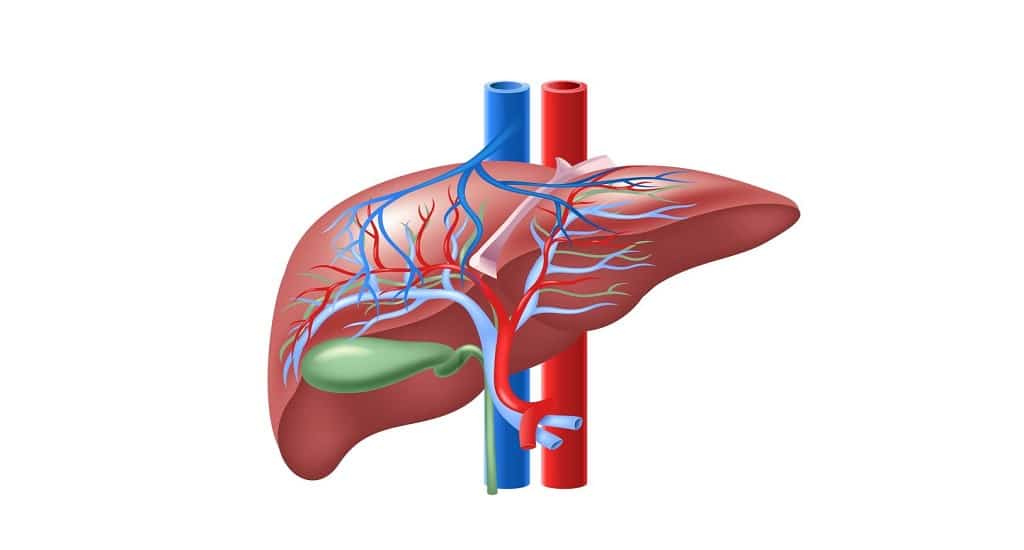

Covid-19: Η δρ Jawaher Alharthi, από το Ινστιτούτο Westmead και την ιατρική έρευνα του Πανεπιστημίου του Σίδνεϊ της Αυστραλίας, και οι συνεργάτες της ανακάλυψαν πώς η COVID-19 αυξάνει τον κίνδυνο λιπώδους ηπατικής νόσου και πώς η τελευταία αυξάνει τη σοβαρότητα της COVID-19, βοηθώντας στην ανάπτυξη πιθανών θεραπειών για τους ασθενείς αυτούς. Η σχετιζόμενη με τη μεταβολική δυσλειτουργία λιπώδης νόσος του ήπατος (MAFLD) επηρεάζει έναν στους τέσσερις ενήλικες και σχεδόν ένα στα δέκα παιδιά παγκοσμίως. Σε παγκόσμιο επίπεδο, η λιπώδης νόσος του ήπατος MAFLD είναι το συχνότερο είδος χρόνιας ηπατικής νόσου.

Η ηπατική νόσος είναι ένας σιωπηλός δολοφόνος. Οι περισσότεροι άνθρωποι δεν γνωρίζουν ότι έχουν ηπατικό πρόβλημα έως ότου αυτό προχωρήσει και αναπτύξουν ουλές στο ήπαρ, κίρρωση του ήπατος και, σε σοβαρές περιπτώσεις, ηπατική ανεπάρκεια και θανατηφόρο καρκίνο. Οι επιπλοκές της, ωστόσο, δεν περιορίζονται στην ηπατική νόσο. Συνδέεται στενά με διάφορες άλλες καρδιομεταβολικές παθήσεις, όπως ο διαβήτης τύπου 2 και οι καρδιαγγειακές παθήσεις. Ως απάντηση στην COVID-19, ο ξενιστής (άνθρωπος) αναπτύσσει μια ανοσολογική απάντηση, η λεπτή ισορροπία της οποίας καθορίζει την πορεία της νόσου. Η σοβαρή COVID-19 σχετίζεται με επιδεινωμένες ανοσολογικές και υπερφλεγμονώδεις αποκρίσεις και τα φλεγμονώδη μακροφάγα μπορούν να προκαλέσουν καταιγίδα κυτοκινών που οδηγεί σε ιστική βλάβη. Μια νέα μελέτη από ερευνητές του Ινστιτούτου Ιατρικής Έρευνας Westmead του Πανεπιστημίου του Σίδνεϊ ανακάλυψε πώς η COVID-19 αυξάνει τον κίνδυνο λιπώδους ηπατικής νόσου και πώς το τελευταίο αυξάνει τη σοβαρότητα της COVID-19, βοηθώντας στην ανάπτυξη πιθανών θεραπειών για τους ασθενείς αυτούς.

Ο Δρ Jawaher Alharthi, πρώτος συγγραφέας της εργασίας αυτής, δήλωσε: “Η σχέση μεταξύ της λιπώδους νόσου του ήπατος και της COVID-19 θεωρείται λίγο μυστήριο, καθώς δεν γνωρίζουμε πώς και γιατί οι δύο ασθένειες αυξάνουν τον κίνδυνο η μία της άλλης. Η ερευνητική μας ομάδα με επικεφαλής τον καθηγητή Mohammed Eslam διεξήγαγε μια μεγάλη και λεπτομερή γενετική και μοριακή μελέτη και εντόπισε ότι το γονίδιο που ονομάζεται MBOAT7 σχετίζεται με τη σοβαρότητα τόσο της λιπώδους νόσου του ήπατος MAFLD όσο και της COVID-19”. “Αυτό το γονίδιο, παίζει σημαντικό ρόλο στη ρύθμιση των ανοσολογικών και φλεγμονωδών αποκρίσεων κατά της COVID-19. Μια διαταραχή στη δραστηριότητα του γονιδίου MBOAT7 θα μπορούσε να αυξήσει τις πιθανότητες αύξησης της παραγωγής κυτταροκινών και της βλάβης των ιστών και της ηπατικής νόσου”, δήλωσε ο Δρ Alharthi. Το επιγονιδίωμα είναι ένα σύνολο δεικτών που καθορίζει όχι μόνο τη γονιδιακή έκφραση, αλλά και τα ίδια τα γονίδια και επηρεάζεται από το περιβάλλον, τη διατροφή και τις ορμόνες. “Είναι ενδιαφέρον ότι εντοπίσαμε επίσης ότι η διακοπή του MBOAT7 μπορεί να “προ-προγραμματίσει” το επιγονιδίωμα των κυττάρων και να τα προετοιμάσει ώστε να ανταποκριθούν έντονα ακόμη και σε μια ασθενή διέγερση κατά της COVID-19 που τελικά αυξάνει τη βλάβη των ιστών”.